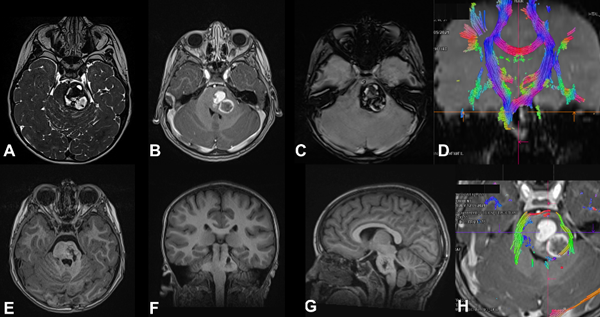

Figura 2. Cavernoma cerebral supratentorial profundo, ubicado en la cabeza del núcleo caudado izquierdo. Paciente femenina de 10 años que ingresa por síndrome de hipertensión endocraneana y primer episodio de sangrado con volcado intraventricular A) requiriendo colocación de drenaje ventricular externo. Evolucionó favorablemente. B) RM cerebral secuencia T2, paciente reingresa a los 2 meses por nuevo sangrado, agregando hemiparesia crural derecha, se decide cirugía programada. C) RM secuencia DTI-tractografía, realizada para planificación quirúrgica. D) RM cerebral, planificación quirúrgica mediante neuronavegación, eligiendo un abordaje transcalloso contralateral. E) y F) RM secuencias T2 y T1 en el postoperatorio, muestran la resección completa. G) y H) Imágenes microquirúrgicas. Se observa la hoz del cerebro y el cavernoma disecado (flecha blanca), en la línea de puntos blanca se observa el lecho quirúrgico con restos de hemosiderina.

Figura 3. MC cerebral infratentorial del tronco del encéfalo. Paciente masculino de 5 años que ingresa por síndrome cerebeloso, asociado a hemiparesia faciobraquiocrural izquierda. Evoluciona favorablemente, egreso hospitalario. A los 2 meses reingresa por un episodio de resangrado. Se decide cirugía programada. A) RM T2 FIESTA que muestra lesión protuberancial, heterogénea, con halo hipointenso. B) RM T1 con contraste EV que muestra sangrado en distintos estadios. C) RM SWI imagen típica. D) y H) RM DTI-tractografía que muestra tractos pontinos transversos en rojo y pedúnculo cerebeloso medio en verde, en este caso se eligió un abordaje supracerebeloso infratentorial lateral y se accedió al cavernoma a través del surco mesencefálico lateral. E-G) RM postquirúrgica de cerebro secuencia T1 en los 3 planos, se evidencia la resección completa de la lesión.